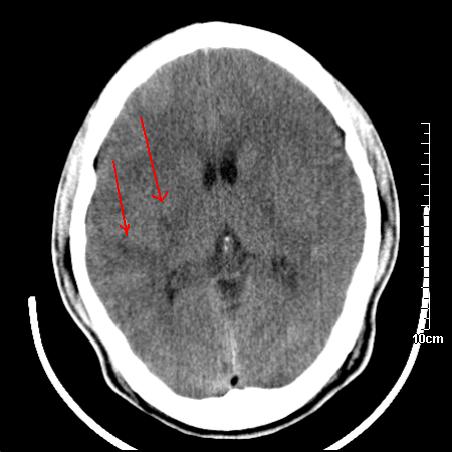

头晕.头痛间断意识恍惚1周 m/21y

4天上述症状加重伴左侧肢体发软,复查ct,

右側额叶、放射冠区灰白质改变,建议ct增强或mri检查

右侧基底节区低密度灶,建议磁共振检查。

右侧放射冠区混杂密度灶,边缘不清,病人较年轻,结合有发热病史,支持感染性病变,建议密切结合临床可抗感染治疗后复查。

右侧颞叶病变定性困难,既然发病急,又有发热,脑脓肿不能除外。

右侧颞叶混杂密度灶,强烈建议:增强ct检查